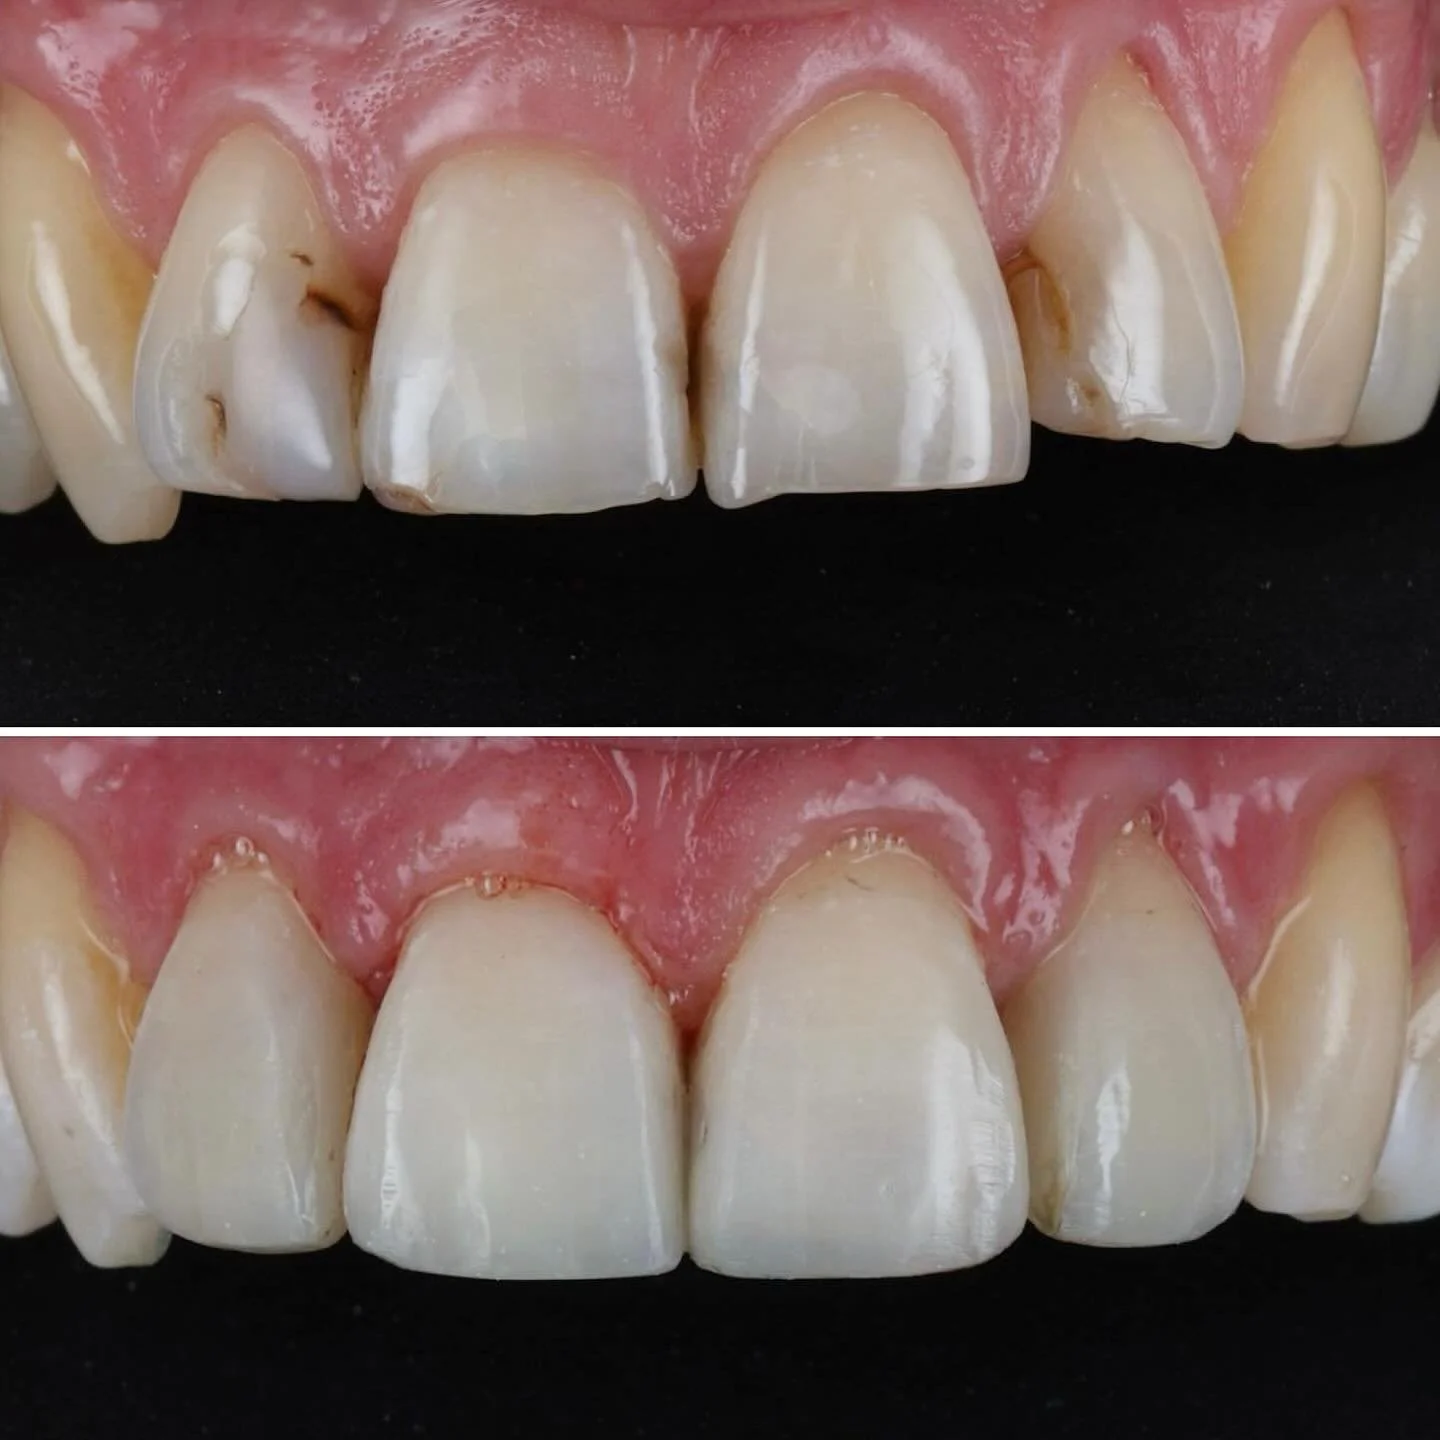

We are an award winning, local family run practice providing advanced implant, cosmetic and family dentistry

We donβt treat teeth, we treat people - you are unique, with individual needs and we have the solutions.